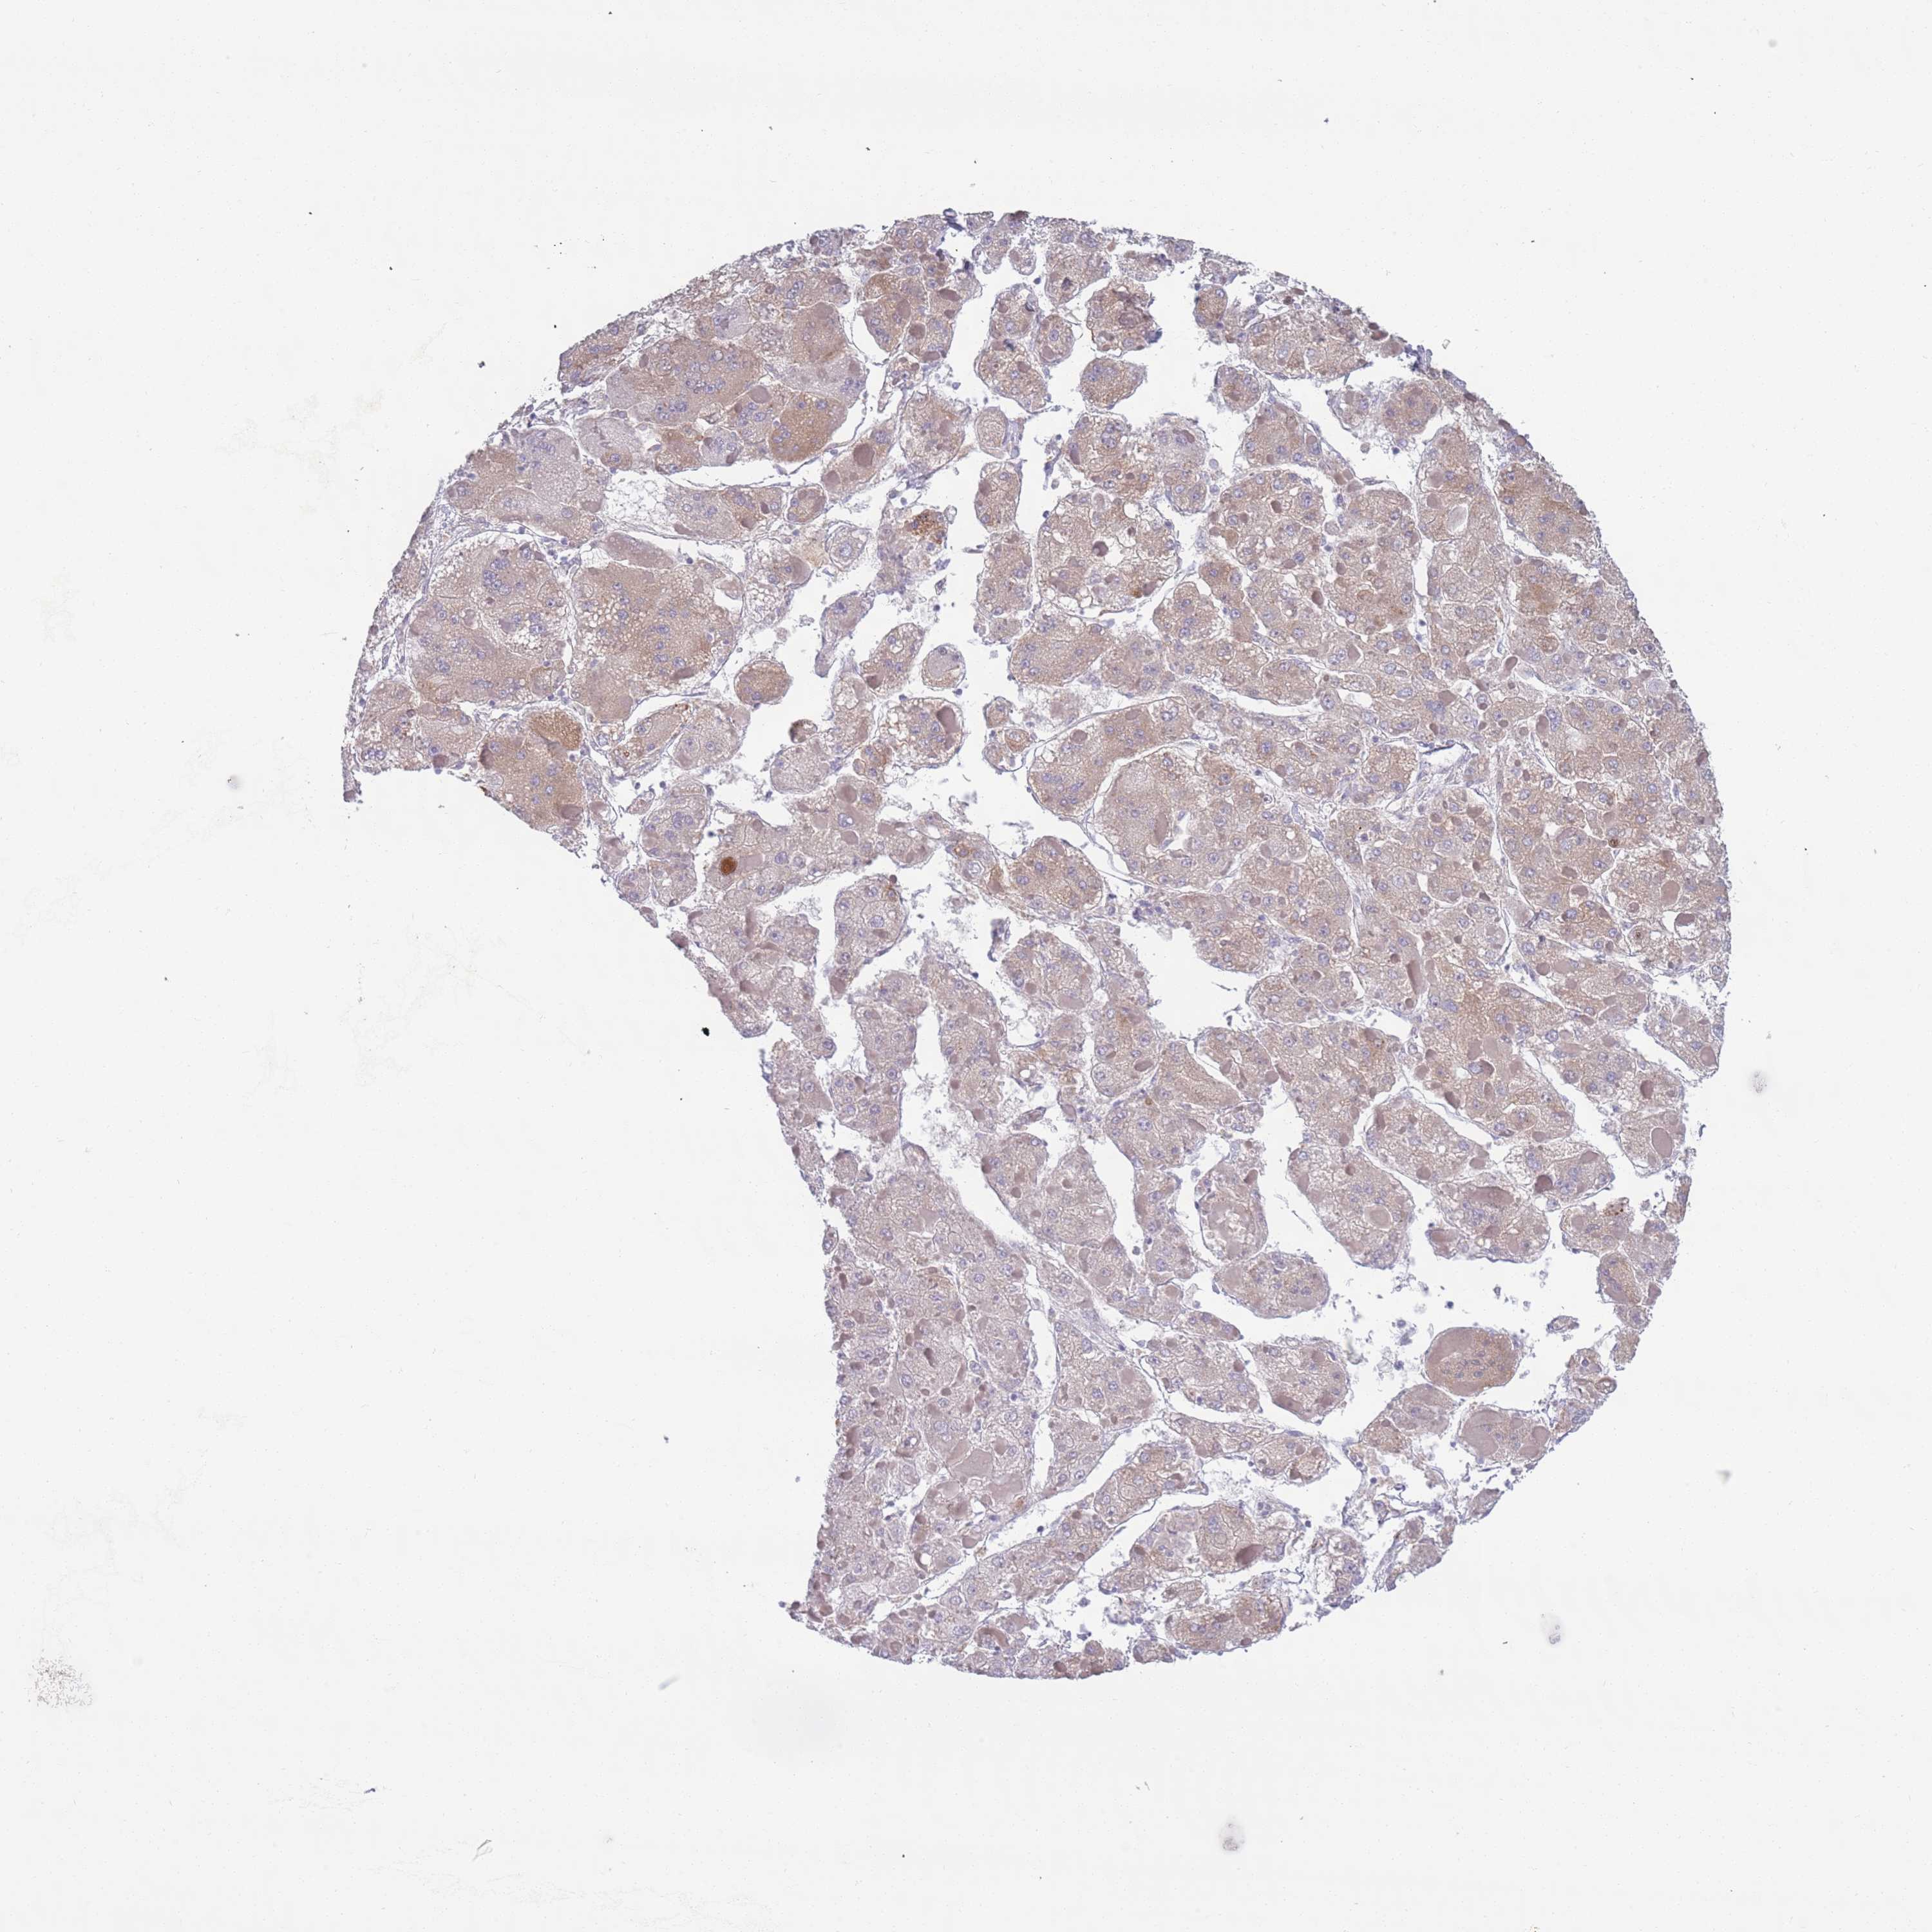

LIVER CANCER - Protein expressioni

A mouse-over function shows sample information and annotation data. Click on an image to view it in a full screen mode. Samples can be filtered based on level of antibody staining by selecting one or several of the following categories: high, medium, low and not detected. The assay and annotation is described here.

Note that samples used for immunohistochemistry by the Human Protein Atlas do not correspond to samples in the TCGA dataset.

Antibody stainingi

Antibody staining in the annotated cell types in the current human tissue is reported as not detected, low, medium, or high, based on conventional immunohistochemistry profiling in selected tissues. This score is based on the combination of the staining intensity and fraction of stained cells.

Each image is clickable and will lead to virtual microscopy that enables deeper exploration of all samples and also displays staining intensity scores, fraction scores and subcellular localization as well as patient and tissue information for each sample.

Antibody HPA048884

Staining

High

Medium

Low

Not detected

Intensity

Strong

Moderate

Weak

Negative

Quantity

>75%

75%-25%

<25%

None

Location

Nuclear

Cytoplasmic/membranous

Cytoplasmic/membranous,nuclear

Cholangiocarcinoma

Carcinoma, Hepatocellular, NOS